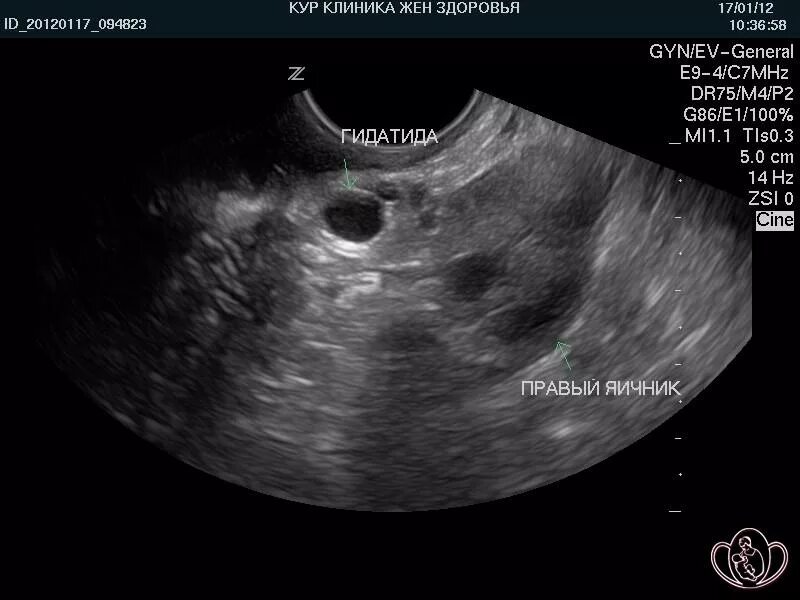

Некроз гидатиды морганьи